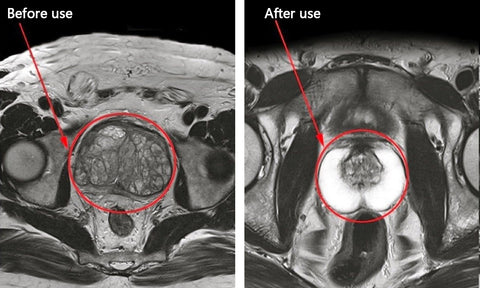

Let us hear John's story with Lancetswell™ Saw Palmetto Prostate Health Supplement

John, a 57-year-old man, had been struggling with prostate issues for quite some time. The discomfort caused by frequent urination at night was taking a toll on his sleep quality and overall well-being.

"I couldn't remember the last time I had a full night's sleep. Waking up multiple times to use the bathroom became a routine, and it was exhausting. On top of that, the constant lower back pain and discomfort in my hips were making it hard for me to find any relief."

"I couldn't remember the last time I had a full night's sleep. Waking up multiple times to use the bathroom became a routine, and it was exhausting. On top of that, the constant lower back pain and discomfort in my hips were making it hard for me to find any relief."

"I used to dread going to bed every night. The constant trips to the bathroom were driving me crazy, and my sleep was disrupted. I knew something had to change. That's when I discovered Lancetswell™ Prostate Health Capsules, and it turned out to be a game-changer for me.

"I used to dread going to bed every night. The constant trips to the bathroom were driving me crazy, and my sleep was disrupted. I knew something had to change. That's when I discovered Lancetswell™ Prostate Health Capsules, and it turned out to be a game-changer for me.

"After reading about the benefits of Lancetswell™ Prostate Treatment Capsules and how it could alleviate prostate issues, I was hopeful that it could provide me the relief I desperately needed. I ordered a bottle and started taking it as directed. "As the days went by, I realized that not only was I getting better sleep, but the lower back pain and discomfort in my hips were diminishing. It was such a relief to feel more comfortable and mobile during the day. I even noticed an improvement in my overall energy levels."

"After reading about the benefits of Lancetswell™ Prostate Treatment Capsules and how it could alleviate prostate issues, I was hopeful that it could provide me the relief I desperately needed. I ordered a bottle and started taking it as directed. "As the days went by, I realized that not only was I getting better sleep, but the lower back pain and discomfort in my hips were diminishing. It was such a relief to feel more comfortable and mobile during the day. I even noticed an improvement in my overall energy levels."